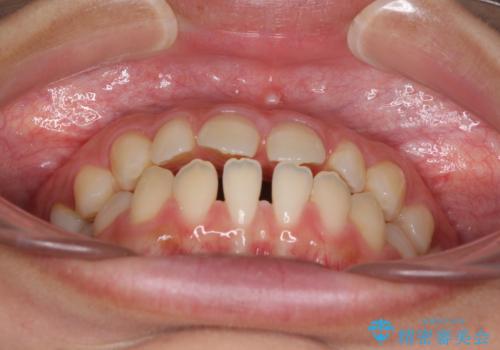

隙間だらけの歯列 インビザラインで改善

- 前歯の上下スペースと前歯の隙間を気にして来院された患者様です。

飲み込みや話をするときに舌を突出させる癖が強くあり、それが原因でスペースが空いていました。

舌癖を改善するためのトレーニングを行いながら、インビザラインにより上下の前歯の隙間を閉じていくこととしました。